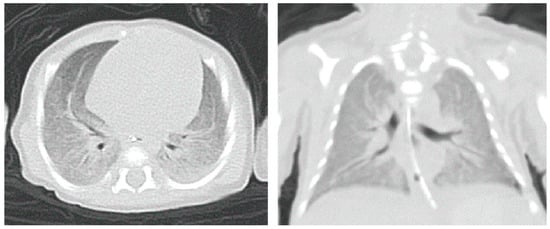

2.3. Accessory Examination

| Polyhydramnios | Severe lung lesions |